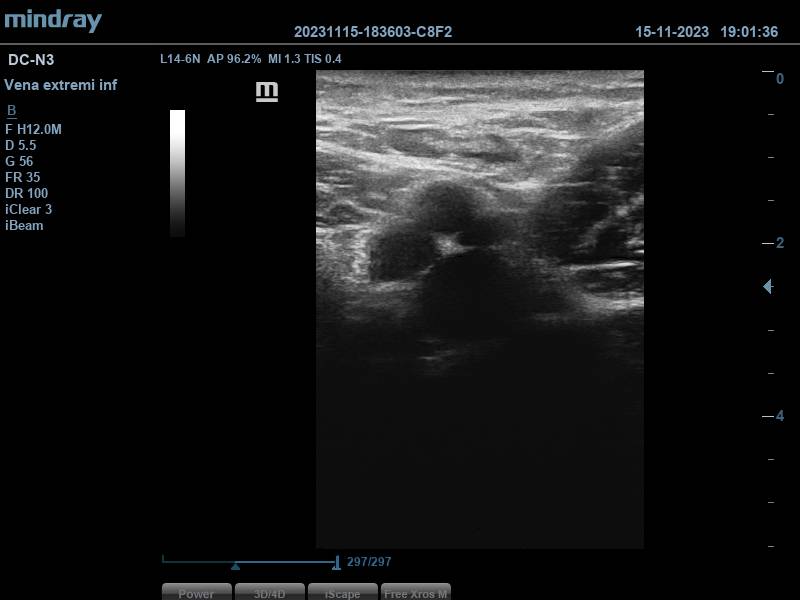

Durante la realización del examen, llama la atención, a nivel de la división de la arteria femoral, en femoral superficial y profunda, aparición de no 3, sino 4 imágenes redondeadas, que sugieren estructuras vasculares.

Se aplica Doppler pulsado, obteniéndose dos espectros compatibles con vasos arteriales (correspondientes a la arteria femoral superficial y femoral profunda), y otros dos espectros con patrón sugestivo de flujo venoso, que aumenta con la compresión del gemelo, generando picos de flujo. Todo ello, hace pensar en que estamos ante una duplicidad femoral.

Ante este hallazgo se procede a realizar la ecografía realizando compresiones por ambas venas femorales, encontrándolas ambas compresibles. Se completa estudio a nivel poplíteo, donde solo se observa una vena poplítea, compresible también.